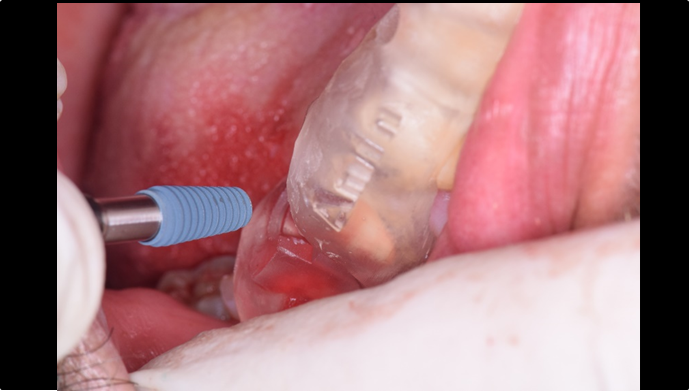

“ One implant /One tooth/ One hour step-by-step

+ associated connective graft ”

Clinical case: EImmediate implant placement & loading of #35 extraction socket with defect

- Courtesy of Dr. Kwang Bum Park, Korea -